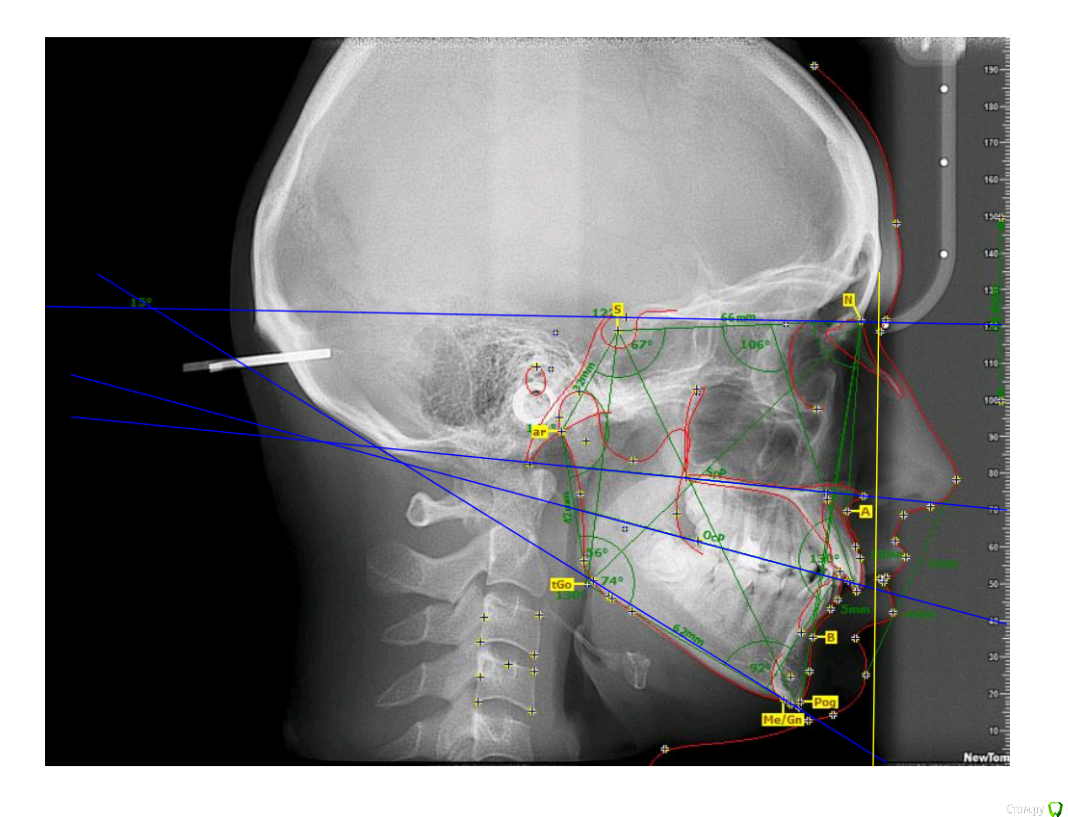

Гелла Опубликовано 15 апреля, 2018 Поделиться Опубликовано 15 апреля, 2018 Возможно ли ортодонтическое лечение без удаления зубов или с минимальным удалением (можно ли ограничиться только нижними восмерками)? Ссылка на комментарий

Monkey Опубликовано 20 апреля, 2018 Поделиться Опубликовано 20 апреля, 2018 Возможно ли ортодонтическое лечение без удаления зубов или с минимальным удалением (можно ли ограничиться только нижними восмерками)? Если лечение будет проводиться без удаления премоляров (а удалять их крайне нежелательно), то удаление верхних и нижних зубов мудрости необходимо. Ссылка на комментарий

Гелла Опубликовано 23 апреля, 2018 Автор Поделиться Опубликовано 23 апреля, 2018 Здравствуйте, спасибо за ответ.Сейчас удаляем нижние зубы мудрости. Верхние зубы мудрости непосредственно "входят" в гайморовы пазухи, для их удаления требуется сложная челюстно-лицевая операция с ушиванием(?) ходов в гайморовы пазухи.Кроме того, все ортодонты, которые консультирование, настаивали на удалении как минимум двух верхних "четверок".Как, по Вашему мнению, стоит ли сохранение "четверо" столь сложной и малопрогнозируемой операции? Ссылка на комментарий

Monkey Опубликовано 23 апреля, 2018 Поделиться Опубликовано 23 апреля, 2018 Здравствуйте, спасибо за ответ.Сейчас удаляем нижние зубы мудрости. Верхние зубы мудрости непосредственно "входят" в гайморовы пазухи, для их удаления требуется сложная челюстно-лицевая операция с ушиванием(?) ходов в гайморовы пазухи.Кроме того, все ортодонты, которые консультирование, настаивали на удалении как минимум двух верхних "четверок".Как, по Вашему мнению, стоит ли сохранение "четверо" столь сложной и малопрогнозируемой операции?Если не хотите в будущем получить проблемы с височно-нижнечелюстным суставом, то, однозначно, стоит. Главное найти грамотного хирурга. Ссылка на комментарий